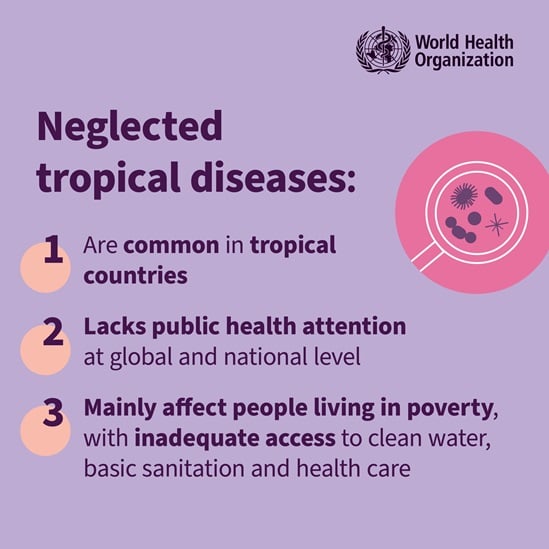

On World Neglected Tropical Disease Day 2024, WHO is calling on everybody, including leaders and communities, to unite and act to address the inequalities that drive neglected tropical diseases (NTDs) and to make bold, sustainable investments to free the estimated 1.62 billion people, in the world’s most vulnerable communities, from a vicious cycle of disease and poverty.

World Neglected Tropical Diseases Day - observed every year on 30 January – aims to spread awareness on the neglected tropical diseases, a diverse group of 21 conditions that are mainly prevalent in tropical areas.